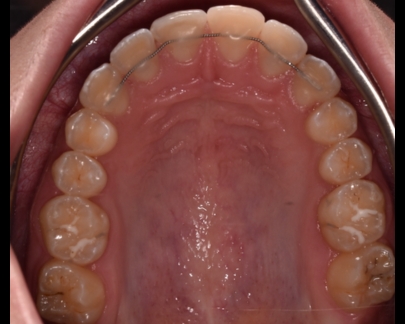

Există două tipuri principale de contenție utilizate în ortodonție: contenție fixă și contenție mobilă.

- Contenția fixă: Acest tip de contenție implică utilizarea unor dispozitive fixate permanent pe dinți.

De obicei, este folosit un fir de sârmă metalică (fir de retenție) care este lipit în spatele dinților,

astfel încât să nu fie vizibil în timpul zâmbetului.

Contenție fixă inferioară |

Contenție fixă superioară |